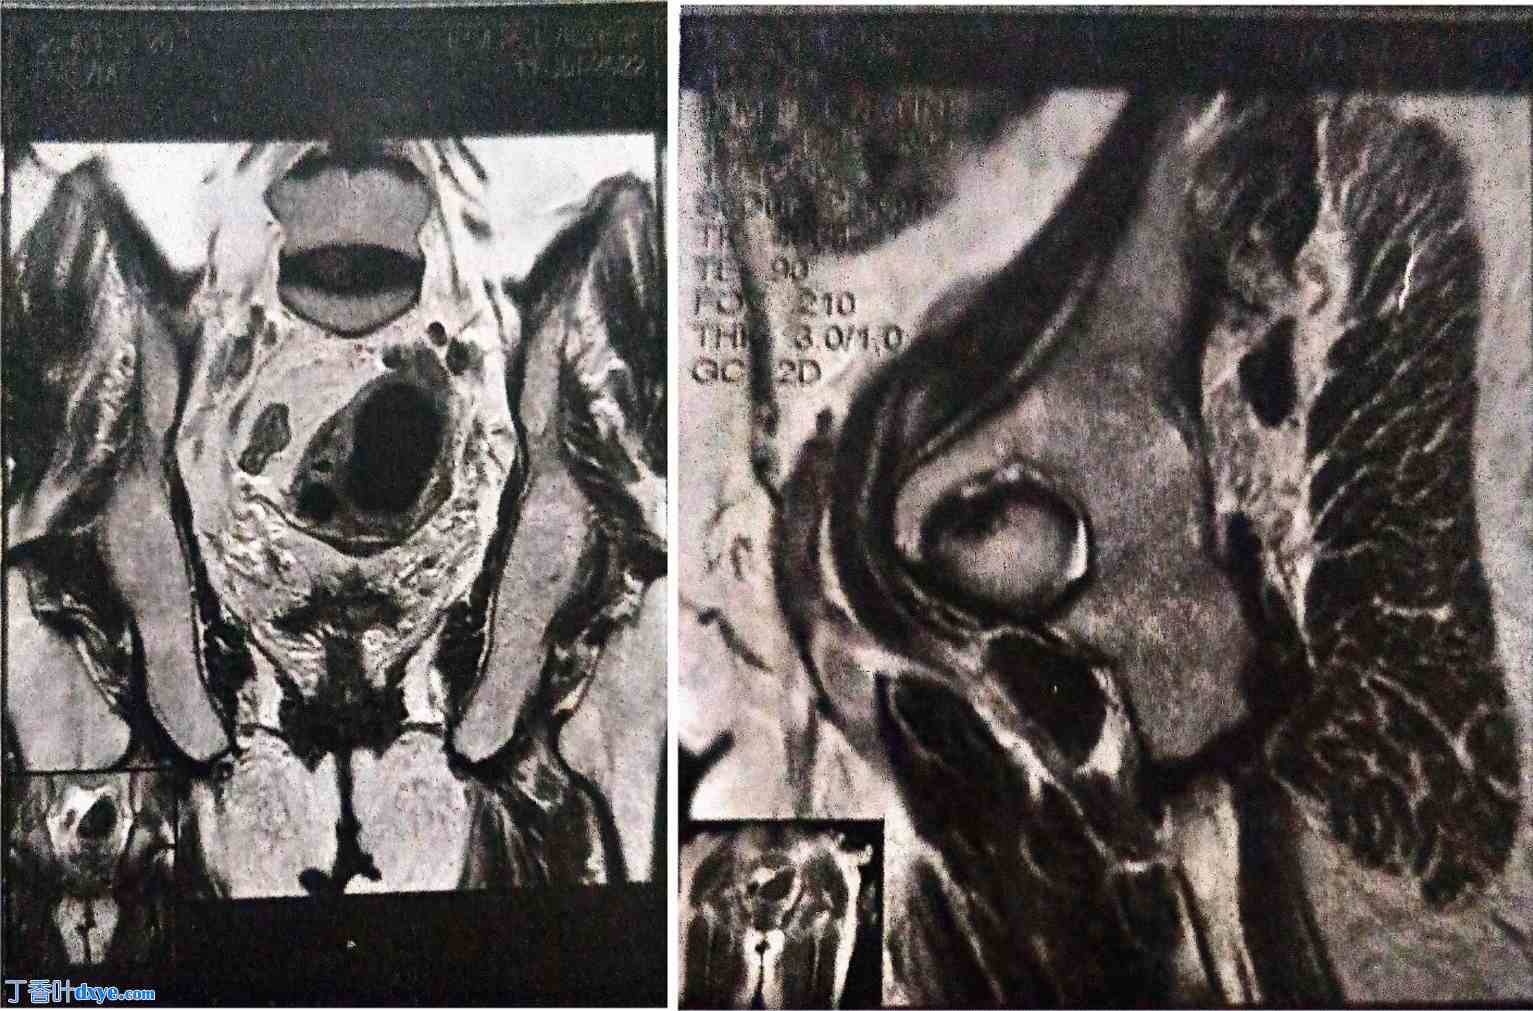

2021年1月,术后随访期间,腹部-盆腔CT扫描时,偶然发现一个4厘米的实性囊性左侧附件肿块,怀疑为恶性肿瘤。经阴道超声和盆腔MRI检查证实该肿块,并被归类为卵巢-附件报告和数据系统(O-RADS) 5级(高度疑似恶性肿瘤)(图1)。

图 1.

腹部-盆腔磁共振成像显示左侧卵巢实性囊性肿块,分类为卵巢-附件报告和数据系统 5